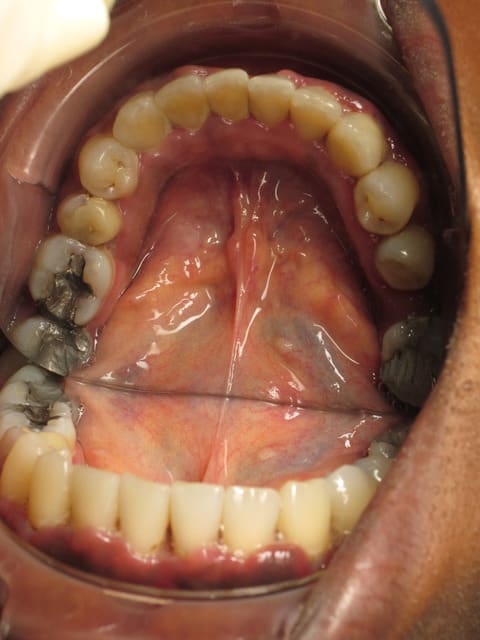

Ci-joint la pano et les photos prises le premier jour (mes premières photos ou presque... c'est pas si facile que ça), je n'ai pas encore les modèles en plâtre.

Arcades xg00l7 - Eugenol

Bas l5icua - Eugenol

Haut fnye5h - Eugenol

elle n'aurait pas une "petite" parodontite ta patiente;)

Ce n'est pas une parodontite, c'est une gingivite.

Vu l'aspect nécrotique de ladite gencive, je dirais mm que ça évoque une GUN.

Et qu'avant d'instrumenter, je baisserai la charge bactérienne qui doit être assez conséquente.

Parce que détartrer dans de telles conditions, ça fait mal, ça saigne comme un boeuf, ça peut cicatriser avec des defects et surtout ça ne résoud pas vraiment le problème parodontal qui menace cette personne

Détartrage + enseignement HBD, et au bout de 10 jours il y a un mieux. Mais il y a pas mal d'obturations défectueuses, rétentives de plaque, à polir/refaire/mettre sous provisoire (je pense à 21 22 par exemple).